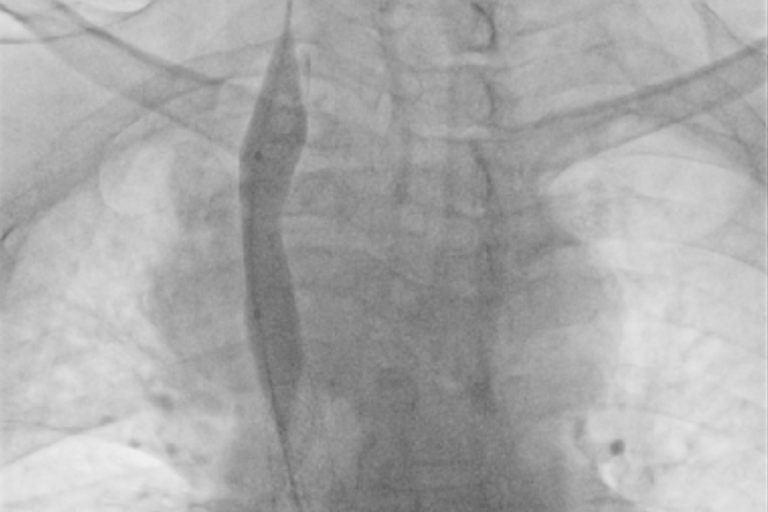

Terapia endovascular de zonas de estenosis

Procedimientos mediante intervencionismo percutaneo para tratar zonas de obstrucción y estenosis responsables de la disfunción del catéter de hemodialisis.

“Nací con hipoplasia renal y, tras un trasplante que falló, tuve que volver a la hemodiálisis. Con los años, mis venas se fueron cerrando y ya no había por dónde dializarme. El doctor me explicó que necesitaban abrir las venas que llegan a mi corazón con una angioplastia de la vena cava. Sonaba complejo, pero confié. Gracias a ese procedimiento y al equipo que lo realizó, hoy sigo en tratamiento y con una nueva oportunidad de vida.”